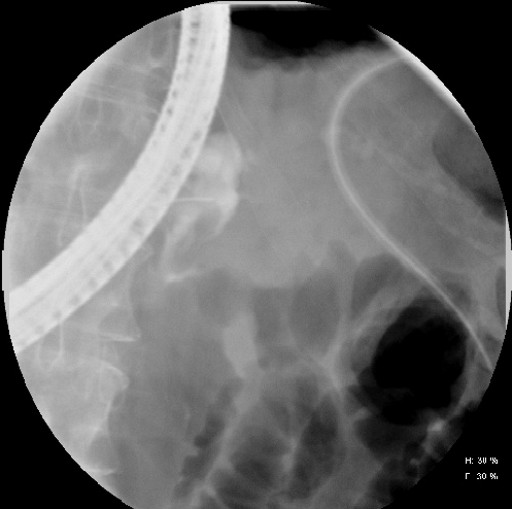

A diagnostic paracentesis was performed that revealed that the serum ascitic-albumin gradient of the fluid was greater than 1.1, with the fluid amylase level being 2,480 U/L, and the lipase being higher than 4,000 U/L. There was no radiographic or biochemical evidence of acute pancreatitis after EUS-FNA. Since the patient required several paracenteses for symptomatic ascites, an endoscopic retrograde pancreatography was performed that showed a significant pancreatic duct leak (Figure 2) at the level of the neck of the pancreas. A 5-French 3 cm transpapillary pancreatic duct stent was placed following which the patients symptoms improved and the ascites resolved over the next few months. A follow-up endoscopic retrograde pancreatography after four months showed resolution of the pancreatic duct leak.

Figure 2. Endoscopic retrograde pancreatographic image of pancreatic duct leak in the neck of the pancreas. |